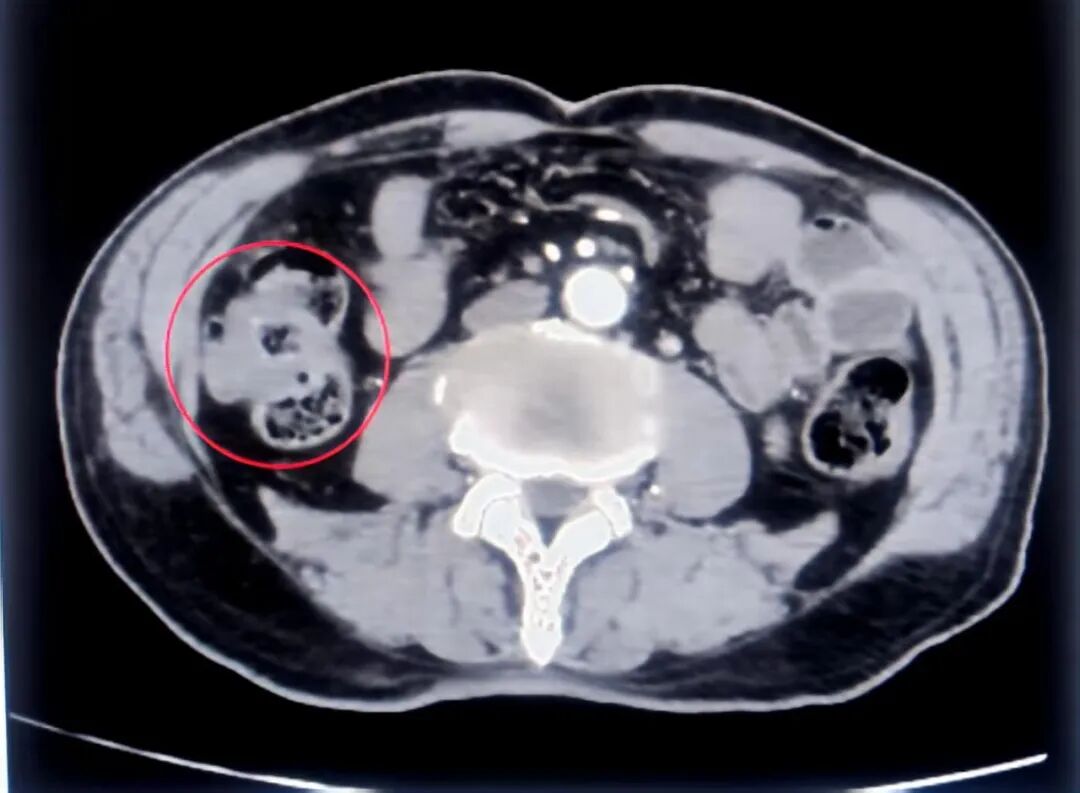

近日,建瓯市总医院多学科协作,运用3D腹腔镜下膜解剖技术,成功救治一例双原发癌复杂病例,使患者既完整切除病灶,又避免全大肠切除和永久造口风险,达成“避免终身造口、微创低损、精准根治、保生活质量”的核心治疗目标。 患者林先生今年 75 岁,因腹痛、恶心、呕吐伴停止排气排便紧急入院。我院胃肠外科团队第一时间为其实施肠道支架置入术,及时缓解了肠梗阻症状,为后续诊疗赢得宝贵时间。然而进一步检查结果显示,患者病情远比预期复杂,不仅确诊降结肠癌,升结肠还存在多发肿物且疑似恶变,属于典型的双原发癌病例。更棘手的是,置入的支架存在下移、脱落风险,加之患者年事已高,身体耐受度有限,常规手术方案极可能需要切除全大肠,导致患者终身携带造口袋,生活质量将大幅下降,手术难度与决策挑战堪称双重考验。 该病例被纳入多学科(MDT)专题讨论,福建省肿瘤医院大肠癌诊治中心主任杨春康团队与我院胃肠肿瘤多学科团队展开深度研判,逐一审视患者检查报告,综合考量病情复杂度、支架安全风险及高龄体质特点,反复推敲治疗方案的可行性与安全性,最终敲定“术前拆除支架+术中定位-直接手术+同步处理双病灶”的精准策略,既确保病灶完整切除,又最大限度保留正常肠段功能,为手术成功筑牢根基。 手术当日,在杨春康团队与我院胃肠外科团队、内镜室、麻醉科等通力协作下,凭借3D腹腔镜下膜解剖技术,结合保留血管的淋巴结清扫术,在复杂的腹腔解剖结构中精准分离、精细操作,成功同步切除左半结肠与结肠肝曲部两处病变组织,实现了病灶的完整切除,同时最大限度保留了正常肠段功能。术后24小时患者即恢复肠鸣音,第3天进流质饮食,无吻合口瘘及感染迹象,标志着高龄双原发结肠癌微创根治术圆满成功。 术后,在我院胃肠外科医护团队的精心照料与康复指导下,患者林先生恢复顺利,各项生命体征平稳,目前已逐步进食并下床活动,朝着康复方向稳步迈进。 近年来,建瓯市总医院持续深化医联体建设内涵,进一步加强学科建设与人才培养,让更多优质医疗资源惠及基层群众。